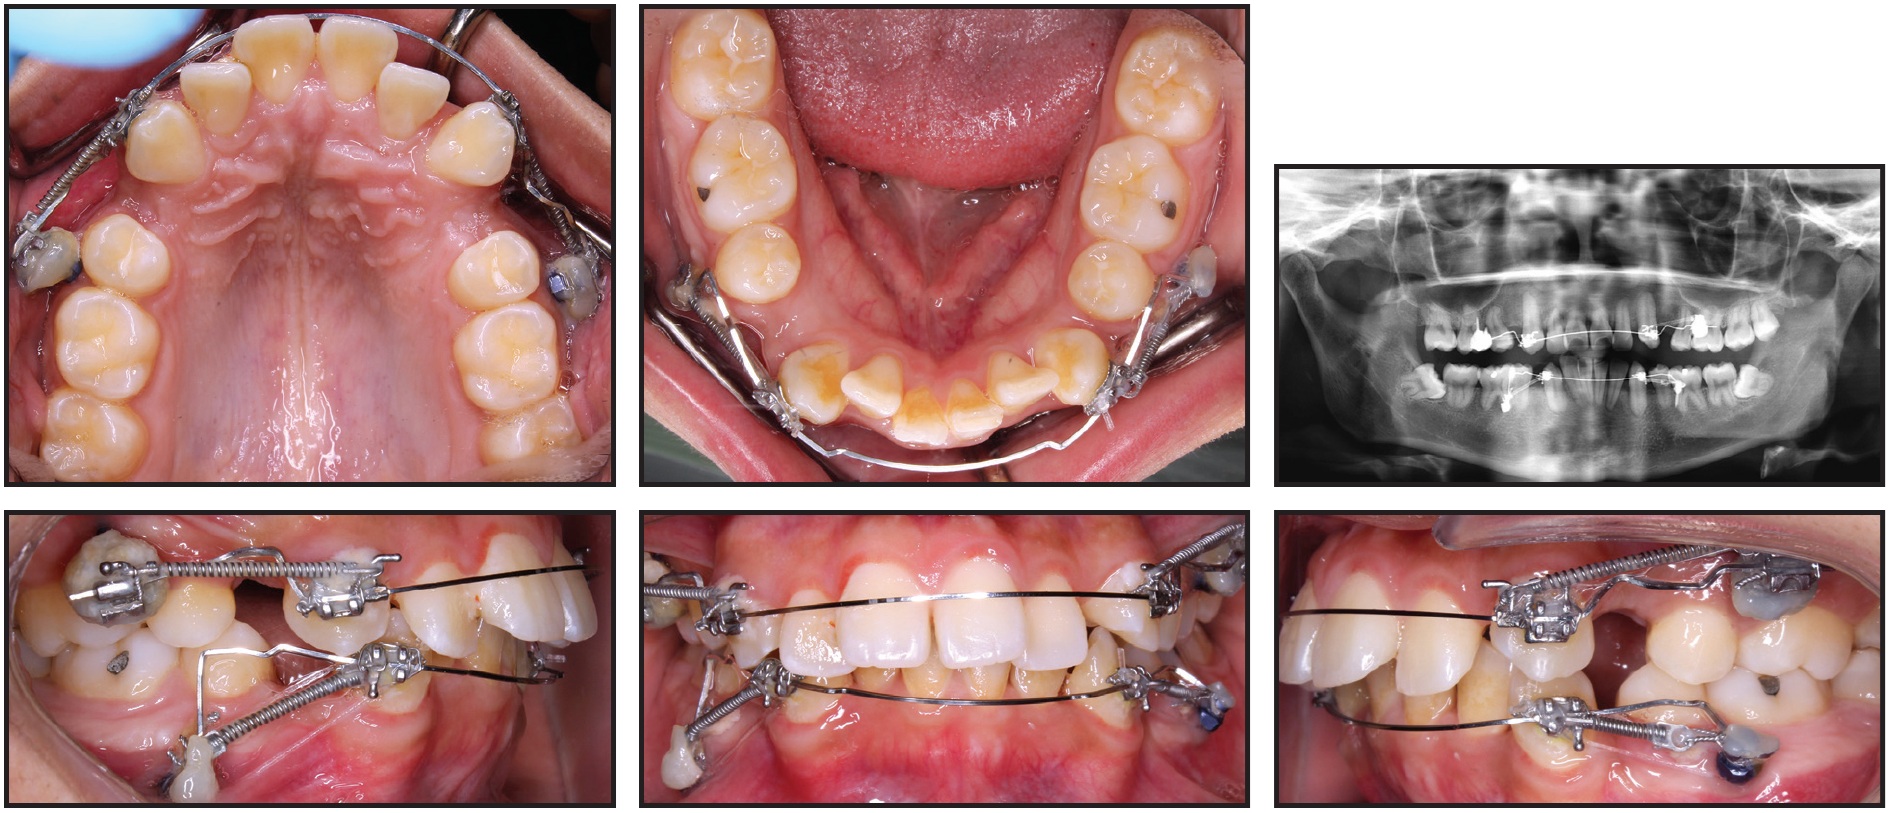

After 11 months of canine retraction, we noted additional spacing in the incisor regions and further spontaneous alignment of the upper and lower incisors, along with substantial movement of the left canines (Fig. 5). Some 3-4mm of space remained distal to the right canines.

Fig. 5 After 11 months of canine retraction, transpalatal arch soldered to upper canine bands and elastomeric chains attached from extension arms to mini-implants.

The maxillary mechanics were then modified for transverse control, with an .030" stainless steel transpalatal arch soldered to bands on the upper canines. Extension arms were soldered to the buccal surfaces of the bands so that the lines of force would pass close to the canine centers of resistance, and canine retraction was continued with elastomeric chains from the extension arms to the mini-implants. The previous mechanics were maintained in the mandibular arch.

Both upper canines and the lower left canine were fully retracted after 20 months of treatment. At this stage, both arches were bonded with .022" preadjusted edgewise brackets, and mini-implants were removed (Fig. 6).

Fig. 6 Both arches bonded with .022" preadjusted edgewise brackets, mini-implants removed, and leveling and alignment initiated after 20 months of treatment.

Over four months of leveling and alignment, archwires progressed to .019" × .025" stainless steel in the maxilla and .017" × .025" beta titanium in the mandible. The residual spaces around the lower right canine and upper incisors were closed with light elastomeric chain, requiring another three months. Finishing bends were added during the last two months of treatment, but the patient wore no intermaxillary elastics for anchorage or finishing. After a total 27 months of treatment, appliances were removed and vacuum-formed retainers were delivered (Fig. 7A).

Fig. 7 A. Patient after 27 months of treatment.

Favorable dental and soft-tissue relationships were achieved, and the patient was pleased with the results. Both arches were well aligned; a Class I buccal occlusion was maintained on the right side, but the avoidance of intermaxillary elastics resulted in a slight loss of anchorage on the left side during final incisor retraction. The overjet was substantially reduced (from 7mm to 2mm), improving the lip position, smile esthetics, and profile. Cephalometric superimpositions indicated a slight decrease in the ANB angle and convexity (Fig. 7B).

Fig. 7 (cont.) B. Superimposition of pre- and post-treatment cephalometric tracings.

The upper incisors were substantially retracted, and the lower incisor inclination was reduced. There was improvement in the lip projection, especially the lower, in relation to the E-line (Table 1). The length of the roots—including those of the canines, which underwent active retraction for about 20 months—was basically unchanged from the initial radiograph (Table 2). Because the lower third molars showed significant mesial angulation, they were recommended for removal, along with the unopposed upper left third molar.